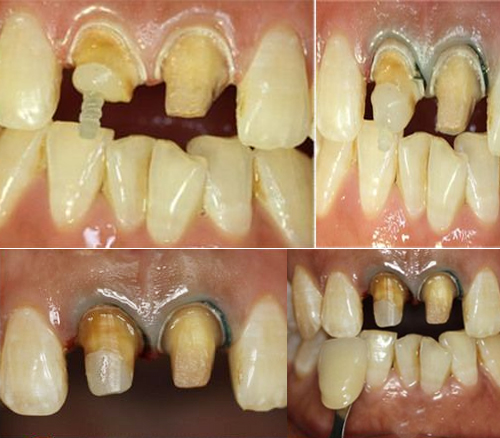

一患者上颌切牙外伤,在外院修复后因变色影响美观,来我院要求重新修复。X线检查发现根充不完善。经植入纤维桩、排龈后恢复牙冠外形、精修肩台、抛光牙体等后,更换新烤瓷牙。经过治疗后的牙齿,分辨不出真、假,患者非常满意。

治疗过程中